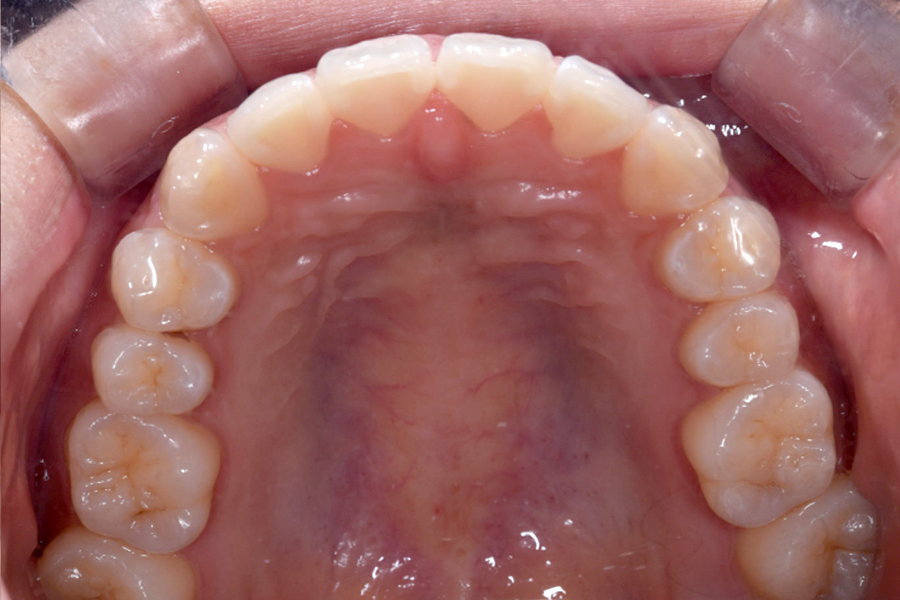

治療前

主訴 上下前歯のすきっ歯が気になる

期間 1年5か月

費用 マウスピース矯正

956,596円(税込)

治療内容 目立ちにくいマウスピース矯正(非抜歯矯正)

歯と歯の間に隙間をつくることにより、歯列弓を広げながら治療を行いました。